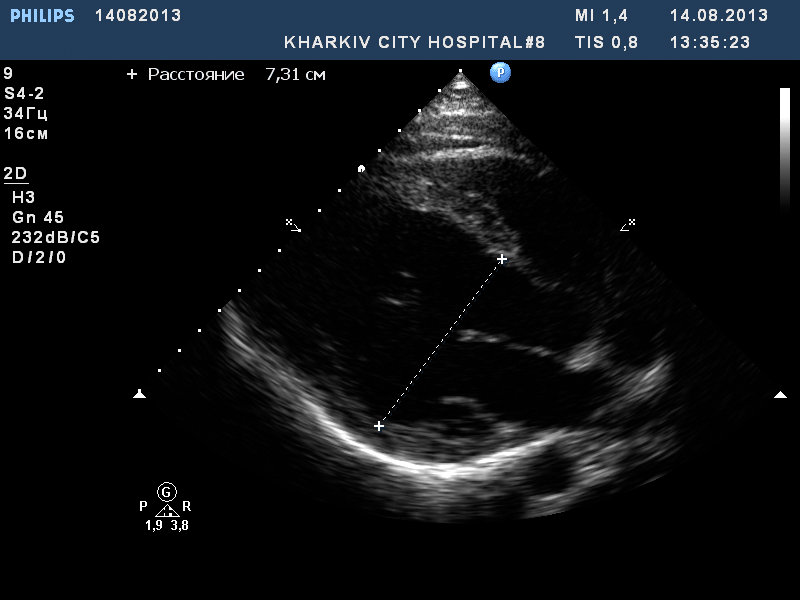

Молодой парень, спортсмен-боксер, на чемпионате в момент сильной физической нагрузки (плюс отмечает что получил сильный удар в область сердца)почувствовал себя плохо. Через время пришел амбулаторно сделать ЭКО-КС. Увидел такую ситуацию: двухстворчатый аортальный клапан с пролабированием и регургитацией, при чем по короткой оси не могу исключить отслоение интимы. дилатирован левый желудочек до 6,4 в диастолу. Рекомендовал консультацию кардиохирурга. Это было полгода назад. Пришел вчера. полость ЛЖ 6,7 в диастолу. Он еще и продолжал тренироваться эти полгода. К кардиохирургам не ездил. Приходил с отцом, у отца мнение, что все что у сына ничего страшного. Внешне сын атлетически сложен, жалоб на момент осмотра нет, как результат отец недооценивает ситуацию. Все таки, думаю, убедил ехать к кардиохирургам. Ваше мнение исходя из некоторых видео.

Сам думаю творчески так: на фоне ВПС-двухстворчатого клапана не произошол ли инцидент в момент сверхнагрузки и возможно произошло отслоение интимы?

я и так понимаю что у него врожденный порок-двухстворчатый АК. И полости я же пишу дилатированы полгода назад были и сейчас. Есть даже отрицательная динамика в расширении левого желудочка. Вопрос по АК по короткой оси и по самой регургитации - нет ли расслоения на данном видео. Восходящий отдел не расширен и отслйка не визуализируется. Мне не нравится странная турбулентность на АК и своеобразный вид двухстворчатого клапана с кровотоком в том месте где он не совсем понятен, скажем так.

Имею в виду, что к врожденному дефекту вероятно добавилось расслоение в момент интенсивной нагрузки\удара... Вот в чем вопрос.

Таки, похоже на отслоение интимы, которое начинает становиться заметным по короткой оси в начале диастолы на 2-х часах. А изменилась ли за полгода регургитация? Если это отслойка интимы, то характер регургитации, причем не только ее степень, но и направление струи регургитации должно было измениться.

Пришел сегодня этот парень. Начал чувствовать себя периодически "не очень" . Отмечает перебои в работе сердца. Надумал ехать в Киев к кардиохирургам на консультацию и дальнейшее оперативное лечение.

Левый желудочек расширился до 7.3 см в диастолу.